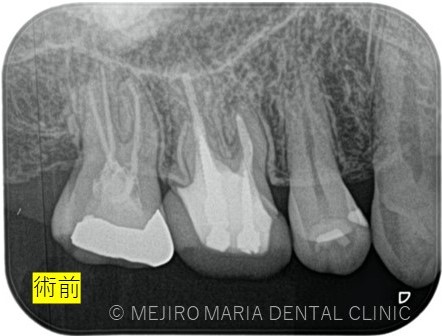

数週間前より右上がうずく感じがすることを主訴に来院された患者様です。近隣の歯科医院でも相談はしたが、特に問題がないと言い渡され、症状が気になり当院を受診されました。

右上7番には臨床症状(叩くことでの痛み)が確認できるものの、レントゲン上には根尖性歯周炎と判断できる透過像(病変の影)は確認できませんでした。歯科用CTを撮影してみると、近心根と遠心根に明らかな病変を認めました(歯科用CT画像1赤丸)。他の臨床症状と歯科用CT画像から右上7番の根尖性歯周炎と診断しました。

また、同時に近心根には見逃している根管もしくはフィンと言われる極小なスペース(CT画像2赤丸)が存在することも確認できます。